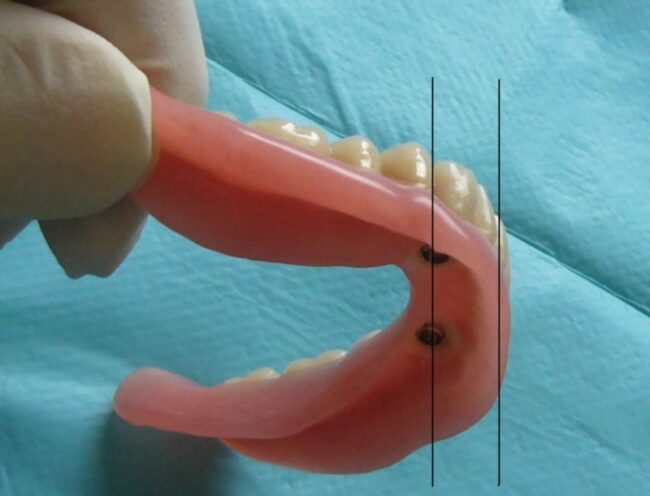

Il arrive que les implants soient placés en émergence relativement linguale pour des raisons anatomiques ou qu’ils ne soient pas parallèles

Dans le cas de boutons-pression (qui sont dans l’axe des implants), un patient peut alors avoir des difficultés à positionner sa prothèse sur les boutons-pression. Cette difficulté peut être insurmontable chez un patient âgé à agilité réduite ou chez un patient nerveux qui risque de détériorer rapidement les parties femelles des attaches !

Il est donc préférable dans ces situations de concevoir une barre : la barre est orientée au laboratoire selon un axe d’insertion prothétique adapté, en l’occurence légèrement vers l’avant :

Le patient est alors beaucoup plus à l’aise pour insérer et désinsérer sa prothèse et les risques de complications mécaniques sont nettement diminués